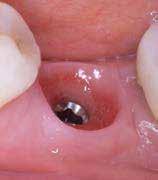

A korai harmicas éveiben járó hölgy rendelőnkbe érkezésének oka a jobb felső nagymetsző fog bizonytalan érzkenysége, elmondása alapján gyermekkorában trauma érte a felső frontrégiót. A frakturált klinikai koronákat kompozittöméssel helyreállították, egyéb kezelést akkor nem tartottak szükségesnek. Az utóbbi hónapokban tapasztalt érzékenység miatt kereste fel rendelőnket. A klinikai vizsgálat (1. és 2. kép) és a CBCT felvétel (3. kép) alapján diagnosztizált külső gyökérreszorpció megoldására a fog eltávolítását, implantátum

bukkális 1. kép: Kiindulási állapot, 2020. január. 3. kép: Kiindulási CBCT felvétel. 2. kép: Kiindulási állapot a palatinális oldal felől.

A behelyeztt implantátum primer stabilitását megfelelőnek ítéltük (kb. 40 Ncm) az azonnali terheléshez (9. kép).

Az extrakciót megelőző szituációs lenyomat alapján gyári, titán, ideiglenes abutment felhasználásával, a szék mellett készített, csavaros rögzítésű, azonnali akrilát ideiglenes koronával láttuk el, melyet 20 Ncm nyomatékkal rögzítettünk (10. kép). Az azonnali terhelés szabályainak megfelelően, az ideiglenes korona nem volt kontaktusban a szomszédos és az antagonista fogakkal.

6. kép: Implantátum-ágy preparáció. 7. a–b. képek: Implantátum behelyezés. 8. kép: A behelyezett implantátum. 10. a–b képek: Azonnali ideiglenes korona készítése. 9. kép: Megfelelő primer stabilitás.